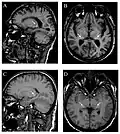

-

Die axiale MRT des Gehirns eines 27-jährigen Morbus-Fabry-Patienten mit ischämischem Schlaganfall zeigt den Schlaganfall in der linken zerebellären Hemisphäre. Der Patient wies sonst keine Symptome der Erkrankung auf. -

Hyperintensitäten der weißen Hirnsubstanz, lakunare Hirninfarkte und Mikroblutungen.

A) Die axiale MRT zeigt vielfältige Läsionen der weißen Hirnsubstanz in der zerebralen Hemisphäre eines 53-jährigen männlichen Patienten mit einem Fazekas-Score von 3.

B) Lakune und Mikroblutungen bei demselben Patienten. -

Die T1-gewichteten sagittalen (A) und axialen (B) MRTs zeigen ein symmetrisch hohes Signal im Thalamus (das sogenannte Pulvinar Sign) eines 66-jährigen männlichen Patienten. (C) und (D), ebenfalls T1-gewichtet, zeigen das Pulvinar Sign bei einem 42-jährigen Patienten. -